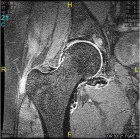

28 year old male with progressive right hip pain for one year

Zoom image: Radiological image Radiological image.